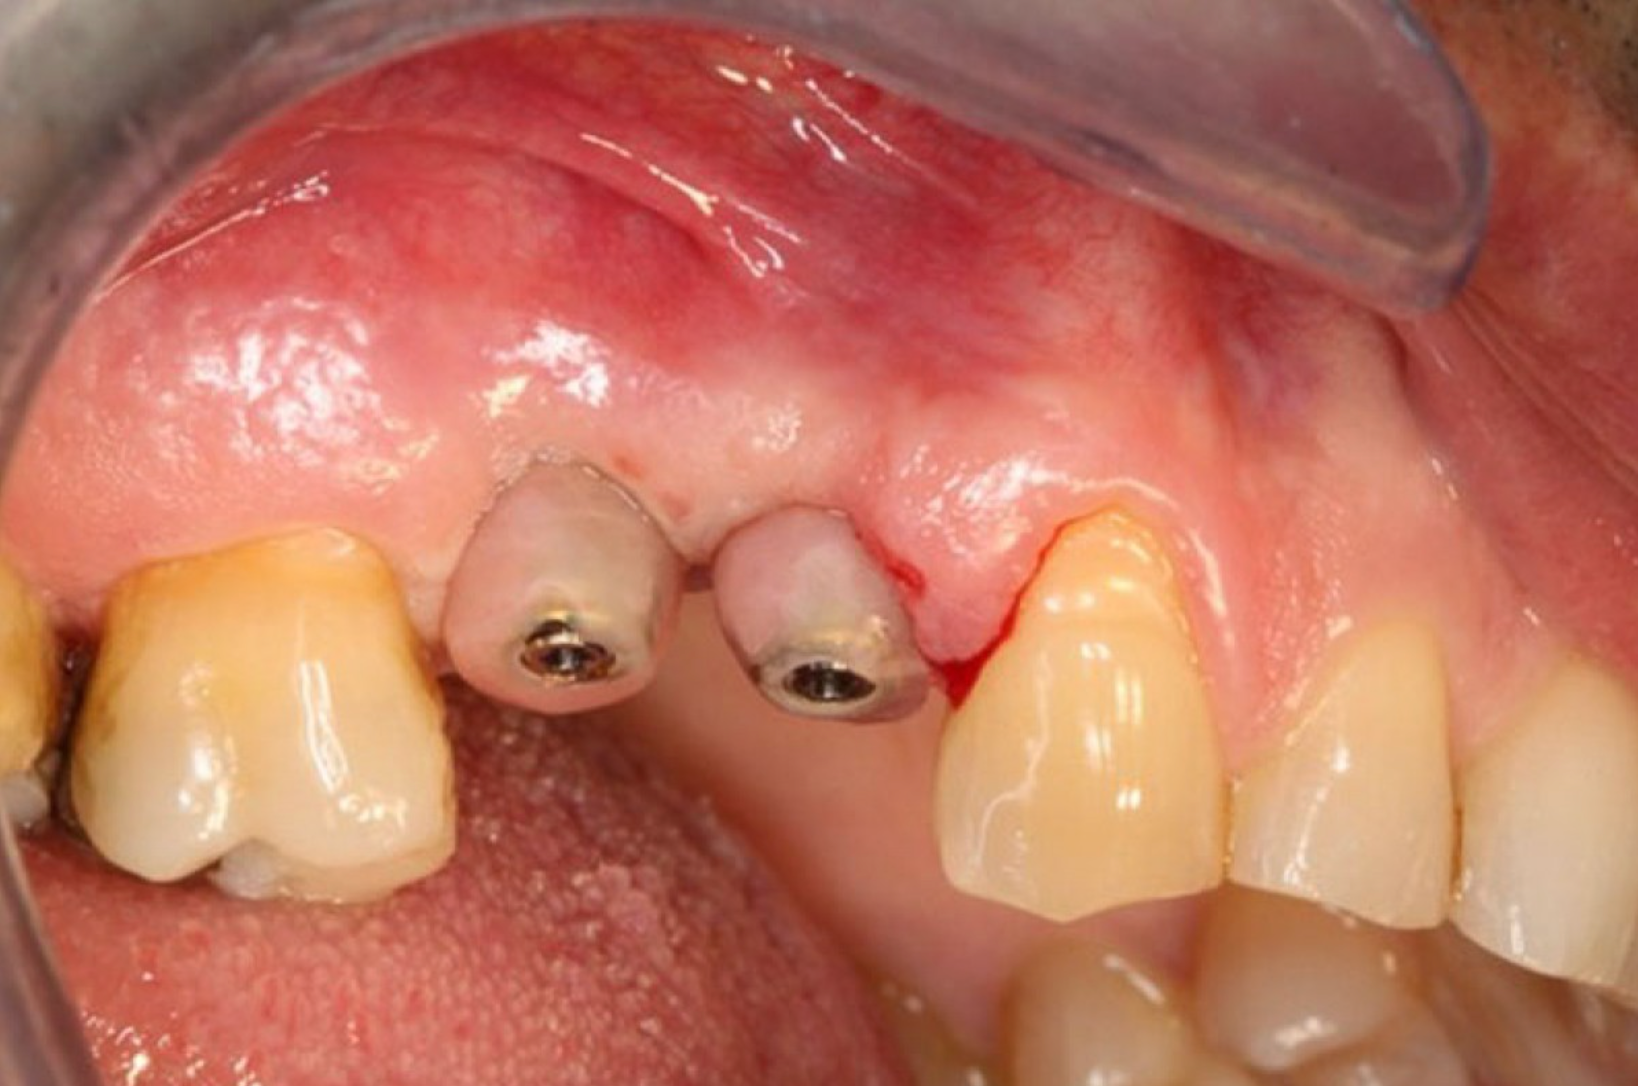

Fase 2: esecuzione chirurgica e finalizzazione. Caso clinico del dott. Massimo Fagnani

Fase 1: la progettazione implantare. Caso clinico del dott. Massimo Fagnani

Il caso del Dott. Monaco con protesi provvisoria di lunga durata a carico immediato